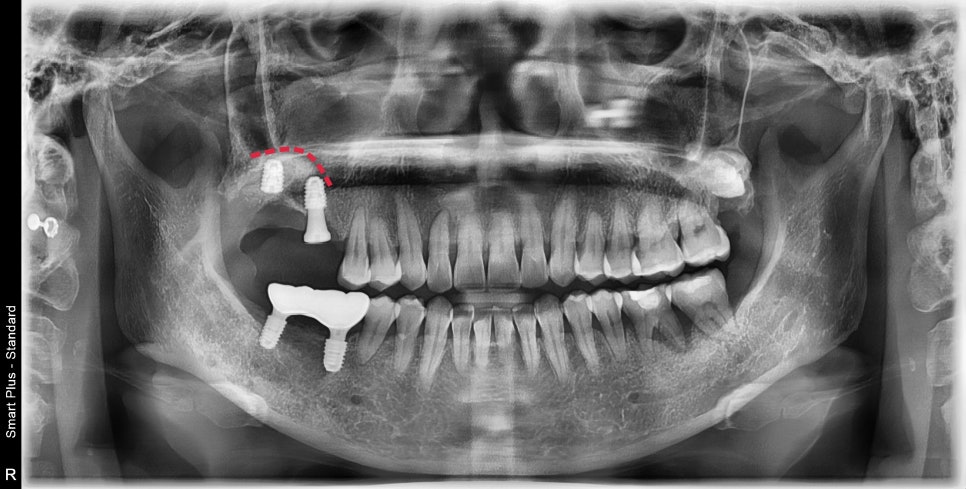

저희 치과에 정기적으로 내원해 주신 환자분이셨습니다.

군데군데 뿌리 주변의 치주질환이 이환되어 있지만 큰 증상은 없어서

잇몸치료와 정기검진으로 증상 체크만 하고 있었습니다.

어느 날 사진에 표시된 오른쪽 위가 찬물에 매우 시리다고 하셨습니다.

엑스레이상에서 뿌리 주변 염증소견이 보여 확실히 확인하기 위해

3D CT촬영을 한 후 설명을 드렸습니다.

해당 부위의 여러 단면을 촬영한 3D CT입니다.

화살표 표시된 부분이 하얗게 뼈로 채워져있어야 할 공간이

염증에 의해 뿌리 주변이 모두 녹아 뿌리가 외부 자극에 그대로 노출이 되어있었습니다.

이미 뿌리 밑단까지 녹아있었기에 해당 치아와 그 옆의 사랑니까지 발치가 필요해 보였습니다.

또한, 그 옆의 치아도 염증이 퍼져 치주 질환에 이환되어 뿌리의 절반이 노출되었습니다.

이 치아 또한 장기적으로 문제가 생길 소지가 높지만 일단 발치 후 증상을 체크하고

시간이 지난 후에 주변이 재생이 안될 경우 발치 가능성을 고지하고 지켜보았습니다.

발치 후 주변조직의 자연치유의 기다림

발치 후 3개월 정도의 시간이 지나서 주변골의 리모델링이 완료된 후의 사진입니다.

예상했던 대로 최후방 치아의 뿌리의 절반이 뼈로 덮여있어야 할 부분이 재생되지 않고 그대로 노출되어 있었습니다.